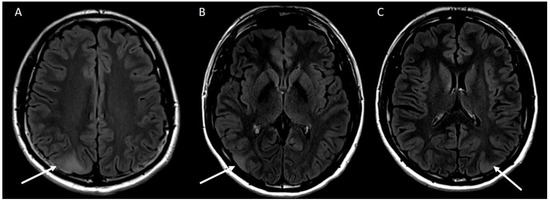

2. Case Report